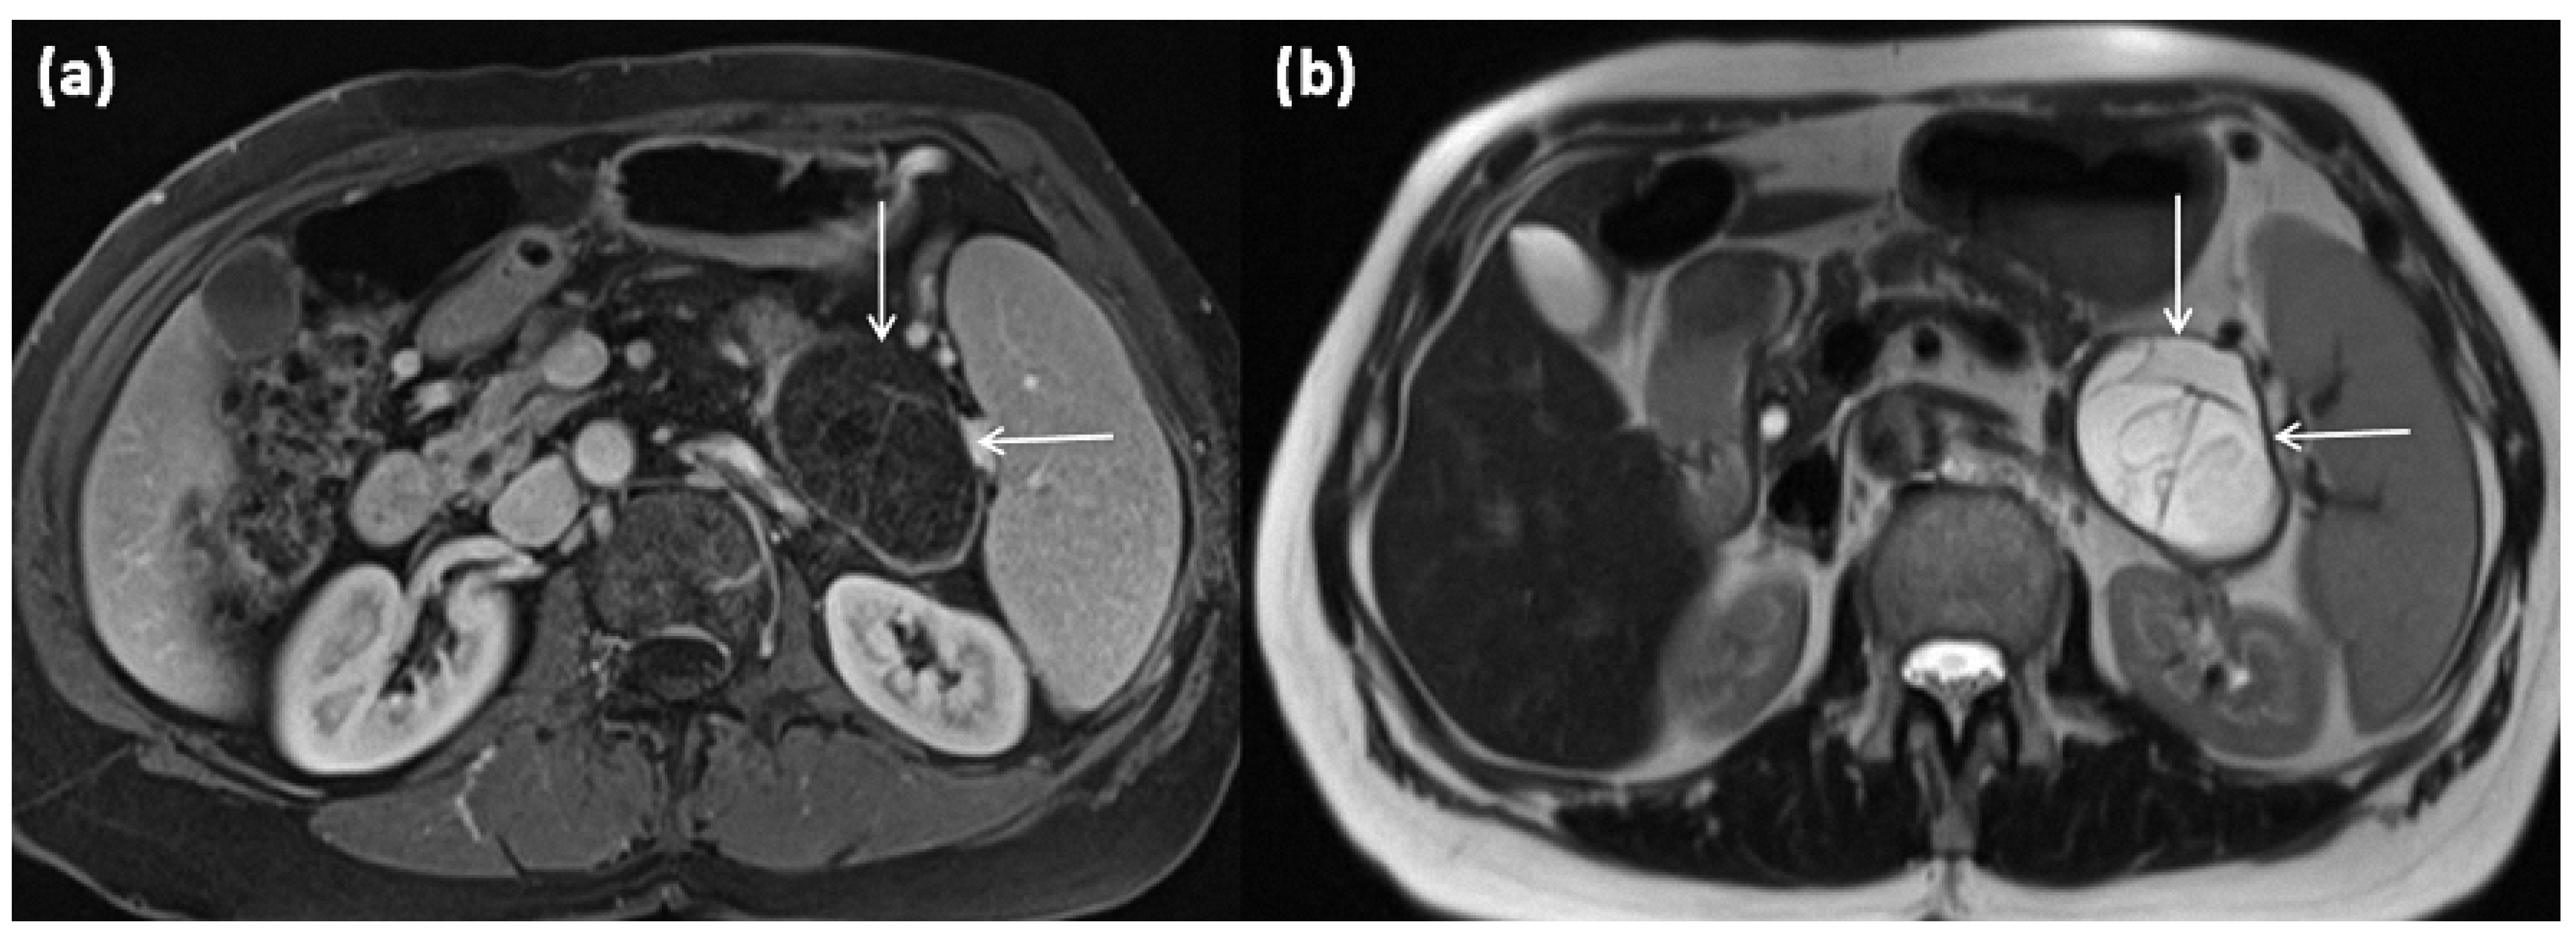

Figure 5.

MRI of a 67-year-old female patient with T1w sequence after gadolinium-based contrast administration (a) and T2w sequence (b). A large multicystic mass of the pancreatic tail (arrows) with tiny septa in T2w, as well as mild contrast enhancement of each septa, is seen.

The often thick cyst walls are well-demarcated in any cross-sectional imaging. MRI usually shows a macrocystic mass, which is usually composed of individual parts often exceeding 2 cm []. The cyst content, typically with a T2w hyperintense signal, may be aqueous, but may likewise be hemorrhagic or have varying protein concentrations with varying degrees of thickening. Therefore, in CT, higher HU values, and in MRI, the variability of native T1 and T2 signals, can be observed. After contrast application, an enhancement of the cyst wall, as well as of the septations, is seen []. In this context, especially in dynamic MRI sequences, an enhancement can be observed, particularly in the later phases due to the fibrous cyst walls; in addition, small mural nodules are possible [,,]. MRCP is mainly used for the differential diagnostic exclusion of a ductal connection, which is not present in MCN.

Peripheral eggshell-like calcifications, which are described as pathognomonic, are rare overall [], but are easier to detect using CT and are considered to be a criterion for a potentially malignant transformation, especially in the case of new occurrence or particularly strong or widely peripheral manifestation []. An occurrence at an older age is suspicious for malignancy as well as large individual cysts of more than 6 cm and irregular and very thick cyst walls with papillary projections in the sense of solid nodular components or hypervascular areas [,,,].